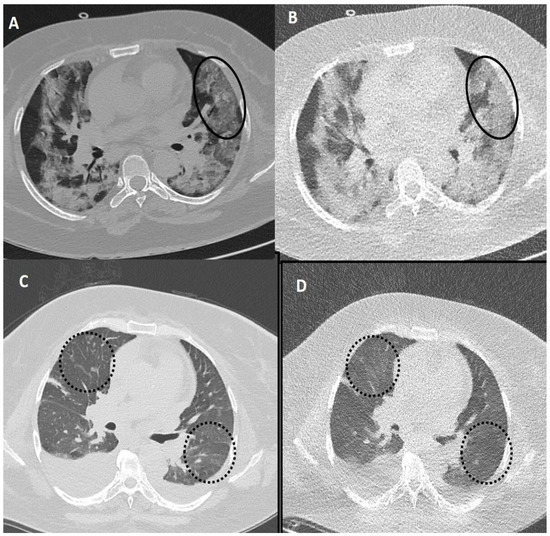

Figure 3.

A 45-years old female patient tested positive for COVID-19. Standard dose CT (SDCT) chest (A,C) and corresponding ultra-low dose CT (ULDCT) chest (B,D) showing areas of GGOs (white circles) and patchy consolidation with air bronchogram (black arrows). Pneumomediastinum was also seen (dotted white arrows). The effective radiation dose for SDCT and ULDCT was 4.13 mSv and 0.25 mSv, respectively, while the CT severity score calculated on both SDCT and ULDCT was similar (19/25).